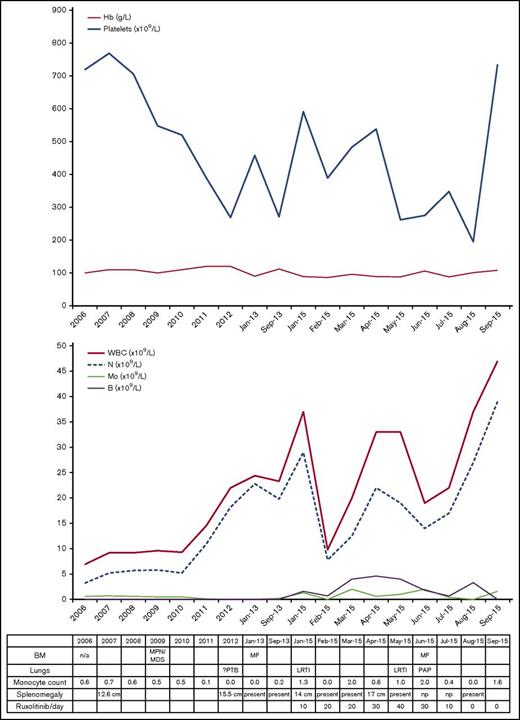

In December 2012, she developed night sweats and weight loss with persistent respiratory symptoms and radiologic findings consistent with mycobacterial disease. She was refractory to standard antibiotics, and although bronchoalveolar lavage (BAL) was smear and culture negative, empirical antimycobacterial therapy led to clinical and radiographic resolution. At this time, she developed a leukoerythroblastic blood film with circulating blasts and intermittent monocytopenia (Figure 1). She lacked mutations of JAK2, CALR, and MPL genes and in 2013 was diagnosed with secondary myelofibrosis based on BM biopsy findings.

Blood and BM investigations and clinical course (2006-2015). Progress of hemoglobin (Hb) and platelet count (top). Progress of white blood cell count (WBC), neutrophils (N), monocytes (Mo), and blasts (B) in the blood (middle). Table listing diagnostic details, absolute monocyte counts, and clinical events (bottom). LRTI, lower respiratory tract infection; MF, myelofibrosis.

Blood and BM investigations and clinical course (2006-2015). Progress of hemoglobin (Hb) and platelet count (top). Progress of white blood cell count (WBC), neutrophils (N), monocytes (Mo), and blasts (B) in the blood (middle). Table listing diagnostic details, absolute monocyte counts, and clinical events (bottom). LRTI, lower respiratory tract infection; MF, myelofibrosis.

In October 2014, she had new chest infiltrates associated with respiratory symptoms, responding to antibiotics. In January 2015, she developed worsening fatigue, splenomegaly, and blood counts showing monocytopenia. Allogeneic stem cell transplant (SCT) was discussed and ruxolitinib commenced. Within 1 month, her symptoms and blood counts improved. Over the next 2 months, the dose of ruxolitinib was increased; her blood counts fluctuated, but splenomegaly resolved in June 2015 (Figure 1).